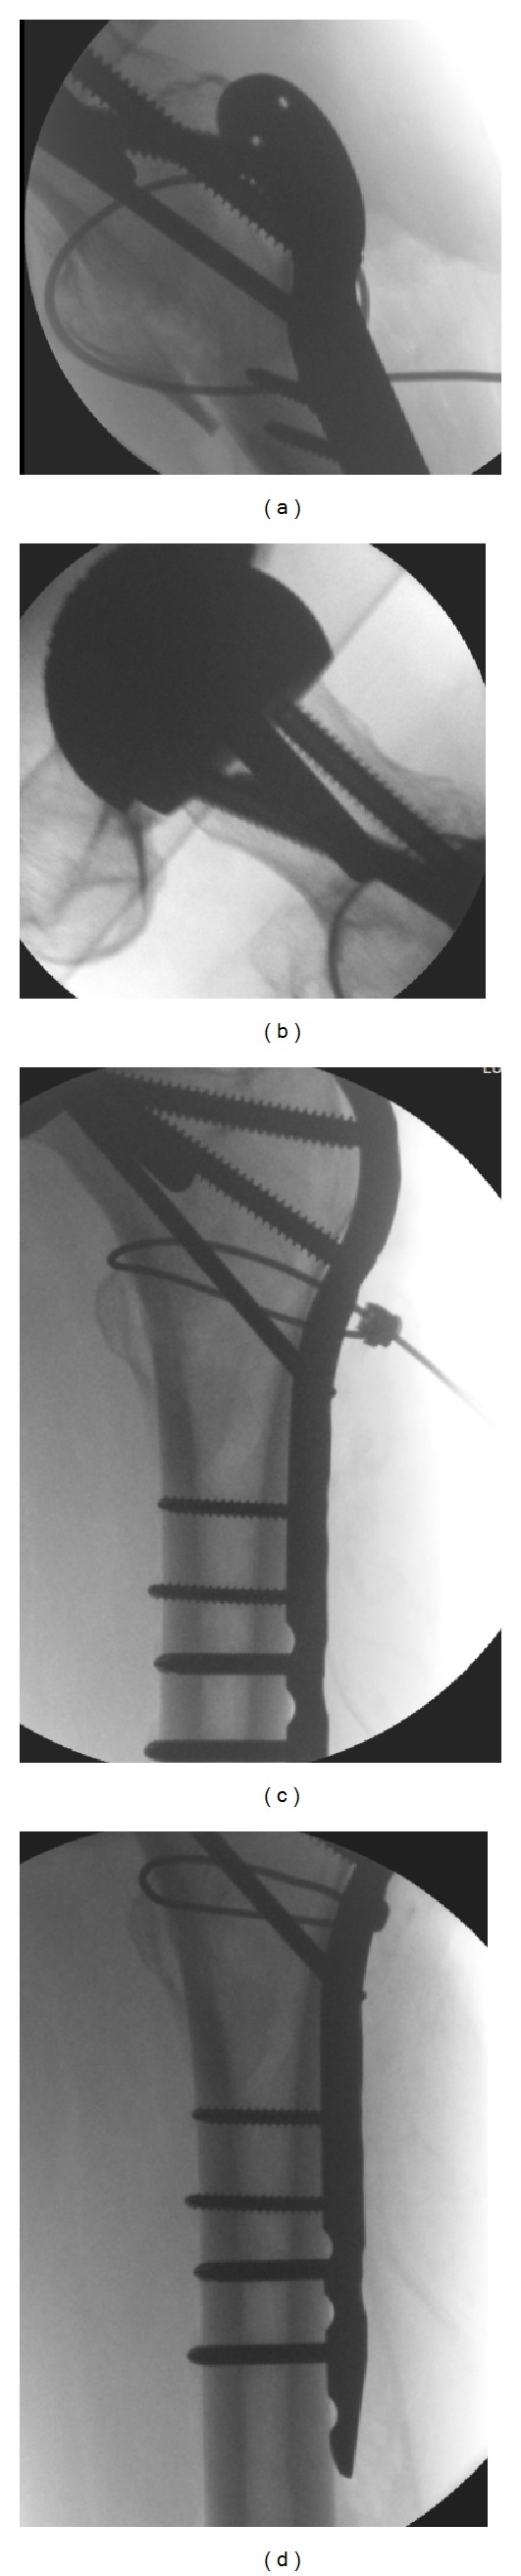

Operative procedure: Mrs X was positioned on the traction table and closed reduction was achieved. Through a lateral approach a LCP proximal femoral plate was placed. A combination of locking and nonlocking screws was used with two passing posterior and one passing anterior to the stem of the Birmingham hip resurfacing prostehesis. Finally, a cerclage wire reduced and held the lesser trochanter fragment. Figure 4 shows the intraoperative screening images.

Figure 4.

(a)–(d) Showing intraoperative screening.